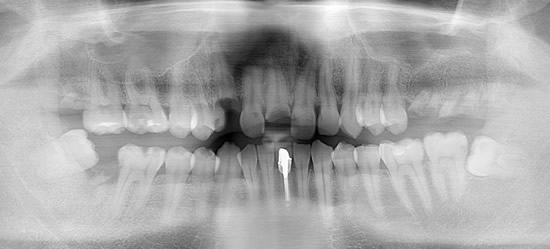

症例5

治療前

インプラント埋入時

治療後

- 年齢・性別

- 35歳男性

- 治療期間

- 3ヶ月

- 抜歯

- 右上1.3左上6.7の残根抜歯

- 治療費

- 123.2万円

- 備考

- 右上1.3左上6.7の欠損部

- 治療内容

- 4本のインプラントを一回のオペで埋入。

- 施術の副作用(リスク)

- オペによる知覚障害。インプラントによる歯肉炎。インプラント脱落。